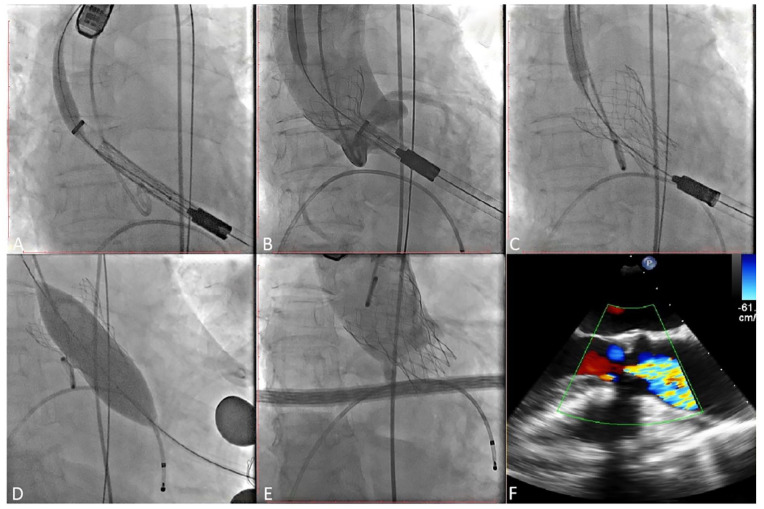

Methods: A total of 9 patients with severe AS accepted TAVR using Xcor system with transapical access in our center. Clinical outcomes were collected at baseline, before discharge, and at the 30-day follow-up.

Results: All patients achieved procedural success, postprocedural transesophageal echocardiography showed that all of the patients had no/trace paravalvular leakage. The mean AV pressure gradient decreased from 50 mmHg (range 18-76 mmHg) to 10 mmHg (range 8-14 mmHg) (P < .001). At the 30-day follow-up, all patients had an improvement of ⩾1 New York Heart Association functional class (P < .001). The average 6-minute walk distance (377.2 [range 330.0-430.0] m vs 276.1 [range 245.0-320.0] m, P < .001) and Kansas City cardiomyopathy questionnaire score (53.4 [range 45.0-62.0] vs 38.9 [range 35.0-43.0], P < .001) were both improved.

Conclusions: Our early experience shows that the Xcor system is safe and feasible in the treatment of patients with severe AS.